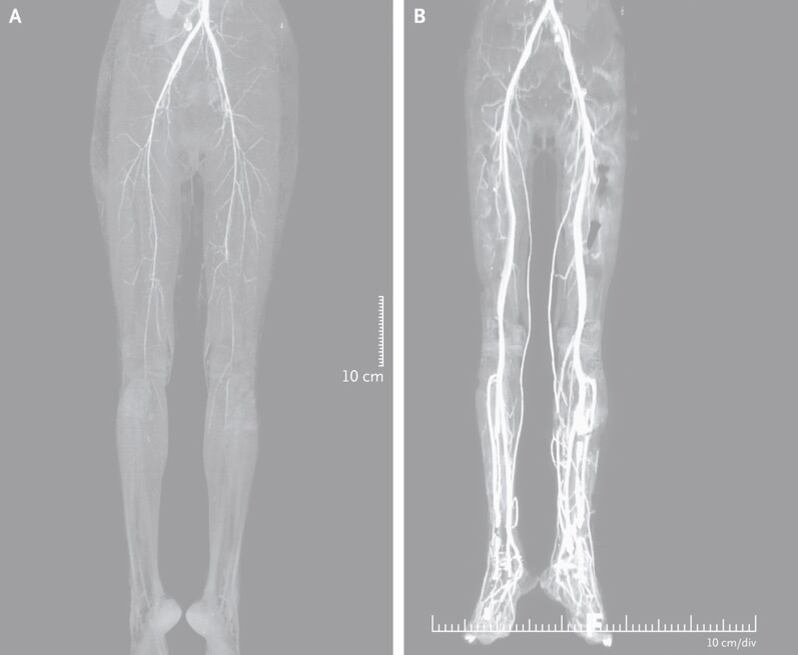

Los médicos se dieron cuenta entonces de que era difícil sentir el pulso de la arteria dorsal del pie y de la arteria poplítea, encargada del riego sanguíneo de la parte inferior de las piernas, así que le realizaron una tomografía computerizada debido a que sus síntomas apuntaban a que se trataba de Ergotismo.